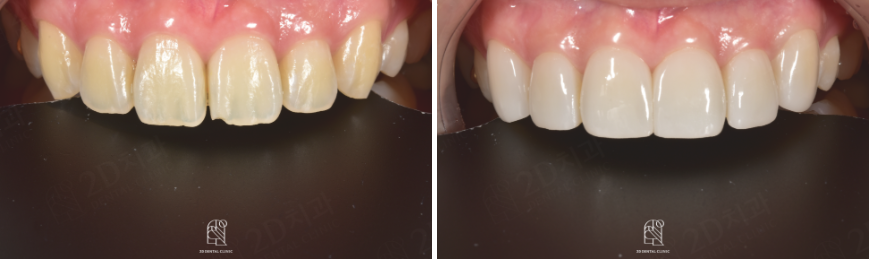

BEFORE

AFTER

앞니깨짐과 같은 상황이 발생하게되면 치아를 상대방에게 보여주지 않기 위해 입을 가리고 웃거나 말을 할때도 발음이 이상해지는 등 다양한 문제가 생길 수 있답니다.

누군가의 얼굴을 마주했을 때 첫 이미지를 결정짓는 요소로 작용하는 치아 그리고 미소. 앞니는 심미성에서 큰 역활을 하기 때문에 문제가 생긴 경우에는 빠른 치료를 진행하는 것이 좋습니다(✿◡‿◡)